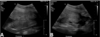

What is shown in these images?

prostatitis -cysts present -fluid/effusion present at caudal aspect in right image